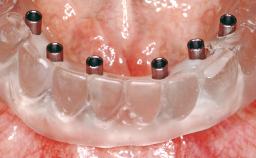

Conventional Loading of Eight Implants in the Maxilla and Final Restoration with a Full-Arch Gold-Ceramic FDP

# of Implants 8

Type of Implants One-Piece